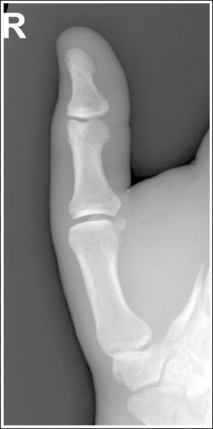

See Figures 4-12 and 4-13 and Box 4-5.

The first digit demonstrates an AP projection. The concavity on both sides of the phalangeal and metacarpal midshafts is equal, as is soft tissue width on both sides of the phalanges.

• An AP projection is accomplished by internally rotating the patient's hand until the thumb is positioned in an AP projection (Figure 4-14). The thumbnail can be used as a reference to determine when the thumb is truly placed in an AP projection. The nail should be positioned directly against the IR and should not be visible on either side of the thumb. A nonrotated AP thumb projection demonstrates equal concavity on both sides of the phalangeal and metacarpal midshafts, as well as equal soft tissue widths on both sides of the phalanges.

• Detecting thumb rotation.When the thumb is rotated away from an AP projection, the amount of midshaft concavity increases on the side of the thumb toward which the anterior surface rotates and decreases on the side toward which the posterior surface rotates. The same observation can be made about the soft tissue surrounding the phalanges when the thumb is rotated. More soft tissue width is evident on the side toward which the anterior surface is rotated, and less soft tissue width is seen on the side toward which the posterior surface is rotated (see Image 10).